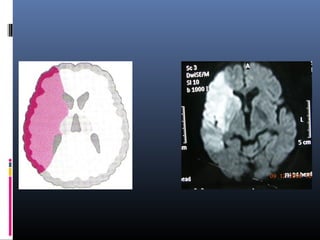

LACUNAR INFARCT

 Lacunar infarcts are small infarcts(less than 15mm)

in the deeper parts of the brain (basal ganglia,

thalamus, white matter) and in the brain stem.

Lacunar infarcts are caused by occlusion of a single

deep penetrating artery.

Lacunar infarcts account for 25% of all ischemic

strokes.

Atherosclerosis is the most common cause of

lacunar infarcts followed by emboli.

25% of patients with clinical and radiologically

defined lacunes had a potential cardiac cause for

their strokes.

 DD WITH VIRCHOW ROBIN SPACES